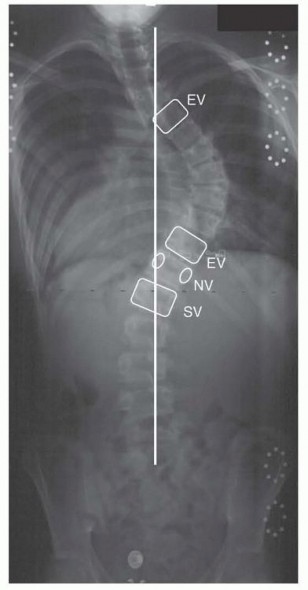

Orthopedic Ob Trauma Review | Dr Hutaif Trauma & Fractu -...